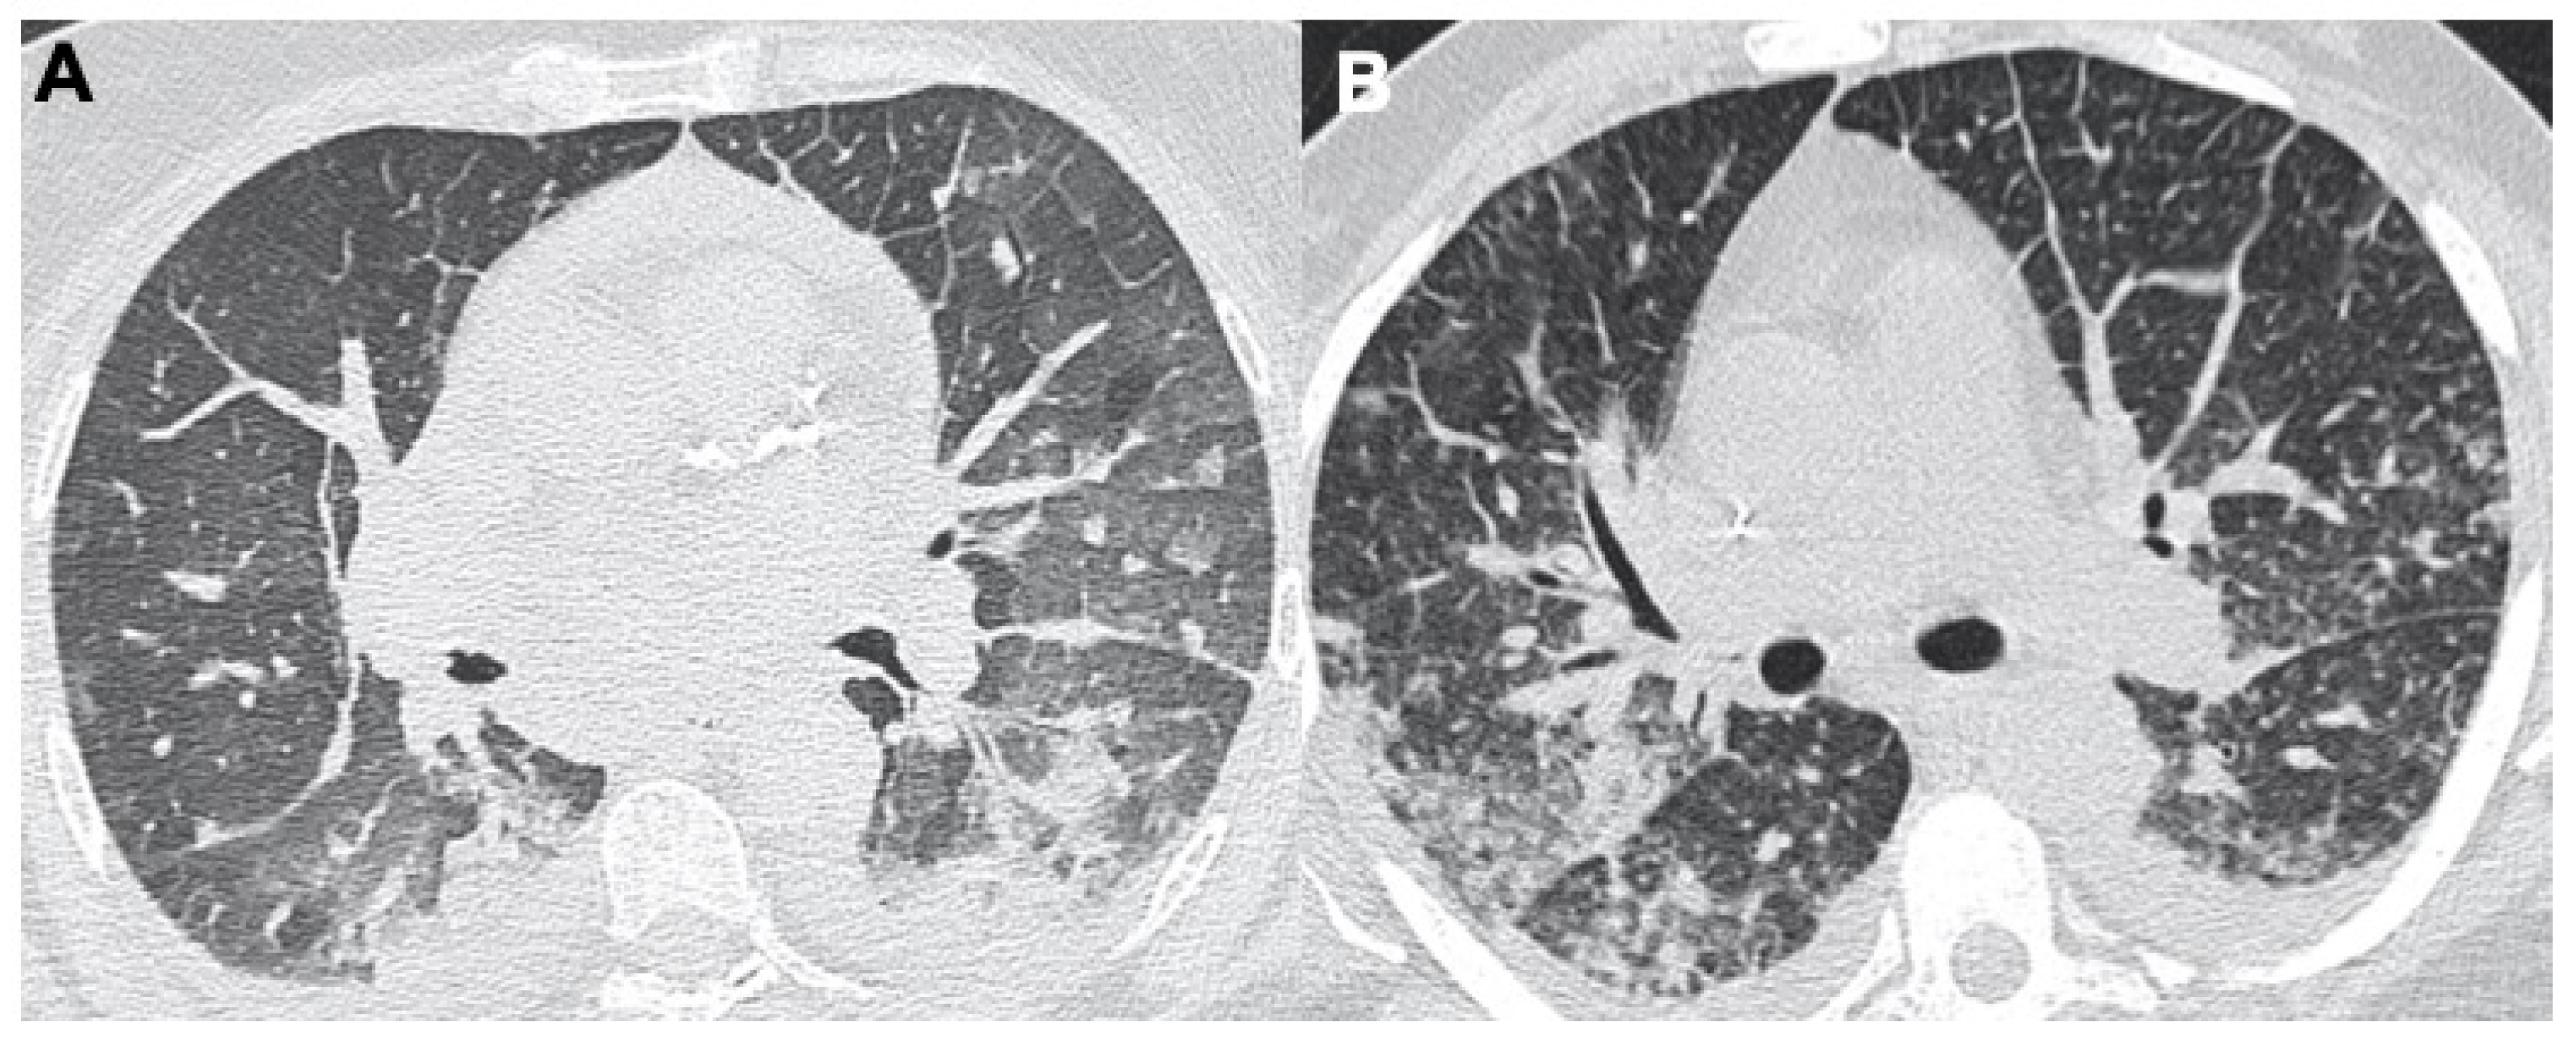

2.1. Pneumonia

- Bernheim, A.; Mei, X.; Huang, M.; Yang, Y.; Fayad, Z.A.; Zhang, N.; Diao, K.; Lin, B.; Zhu, X.; Li, K.; et al. Chest CT Findings in Coronavirus Disease-19 (COVID-19): Relationship to Duration of Infection. Radiology 2021, 295, 200463. [Google Scholar] [CrossRef] [PubMed] [Green Version]

- Carotti, M.; Salaffi, F.; Sarzi-Puttini, P.; Agostini, A.; Borgheresi, A.; Minorati, D.; Galli, M.; Marotto, D.; Giovagnoni, A. Chest CT features of coronavirus disease 2019 (COVID-19) pneumonia: Key points for radiologists. Radiol. Med. 2020, 125, 636–646. [Google Scholar] [CrossRef] [PubMed]